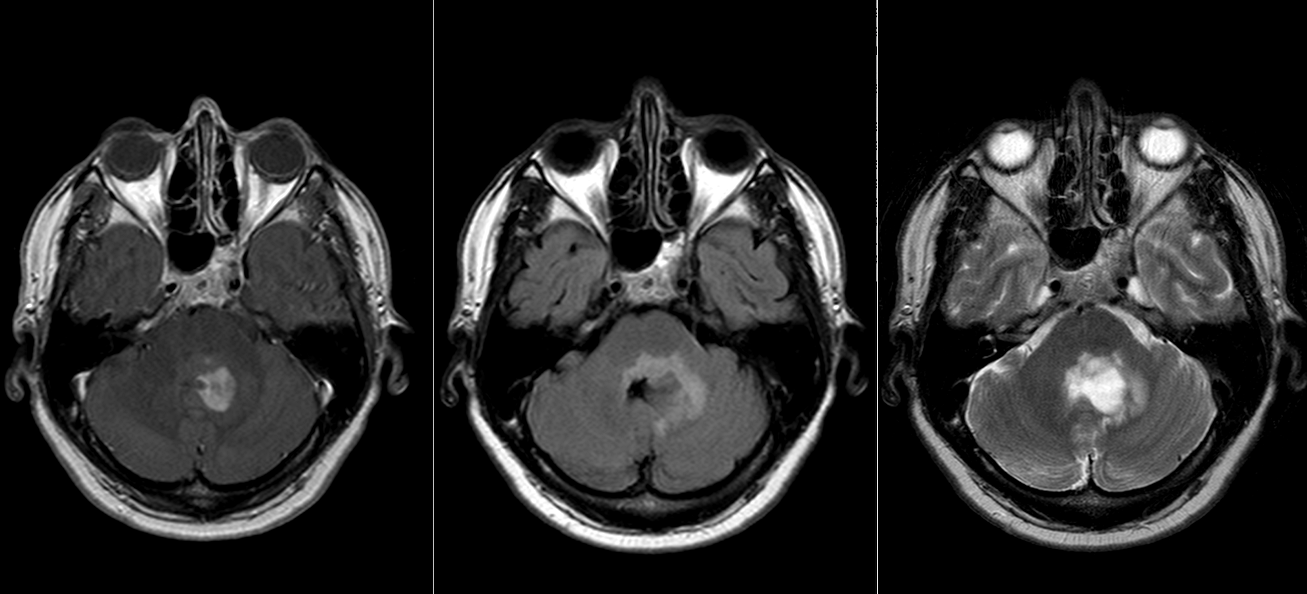

Infratentorial (fosa posterioară) – cel mai frecvent la copii, localizat de obicei în ventriculul IV

Ependimoamele fosei posterioare (infratentoriale):

Semne de hipertensiune intracraniană: edem papilar (la examenul fundului de ochi), cefalee, greață, vărsături – datorită hidrocefaleiie obstructive care însoțește adesea ependimoamele de ventricul IV

Ataxie, dezechilibru, tulburări de coordonare și mers – datorită suferinței cerebeloase

Semne de nervi cranieni: disfagie (dificultăți la inghițit), sughiț, torticolis, diplopie (vedere dublă prin pareza nervului abducens)

RMN cerebral și/sau spinal cu gadolinium este standardul de aur. Tumorile apar ca mase bine delimitate, care pot conține chisturi și zone de necroză. Adesea pot conține microcalcificări (vizibile mai bine pe CT). Datorită localizării intraventriculare, ependimoamele pot determina obstrucția circulației lichidului cefalo-rahidian și hidrocefalie.

Pentru pacienții care nu pot efectua RMN, tomografia computerizata (CT) este utilă, dar tumorile de mici dimensiuni pot trece neobservate.

Diagnostic diferențial

Ependimoamele trebuie diferențiate de alte tumori cu localizare ventriculară sau în fosa posterioară:

Meduloblastom

Astrocitom pilocitic

Metastaze

Tumori neuroectodermale primitive

Papilom de plex coroid

Diagnosticul diferențial se face pe baza imagisticii, histologiei și, tot mai important, pe profilul molecular.